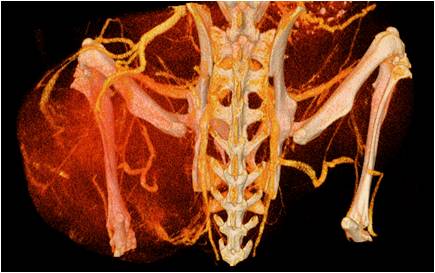

能進行全身血管成像研究,獲得高分辨率的血管造影影像;

胸部和心血管的層析成像 胸部和心血管的3D圖像